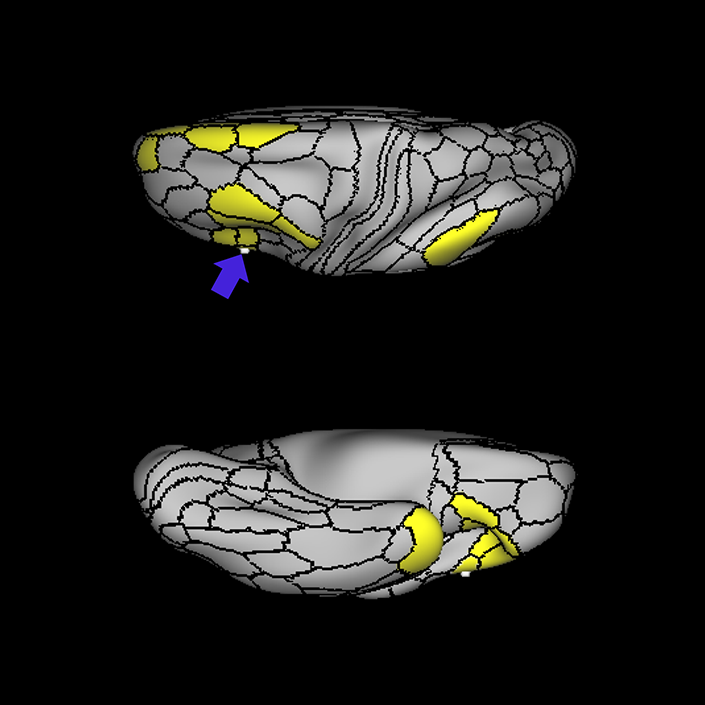

ᐅ SummaryArea 55b: part of the premotor areas. Relatively uncharacterized regions. In 1956, one of the only studies to characterize this regions concluded that the area played a role in language processing. ᐅ Where is it?Area 55b is located on the anterior half of the precental gyrus, approximately half way down its length along the convexity, just inferior to FEF. It also forms the adjacent floor of the precentral sulci and straddles slightly onto the posterior edge of the middle frontal gyrus. ᐅ What are its borders?Area 55b borders area FEF superiorly and PEF and area 6v inferiorly. Area 4 is its posterior border and areas 8AV and 8C form its anterior border across the precentral sulcus. ᐅ What are its functional connections?Area 55b demonstrates functional connectivity to area 4 in the motor strip, areas SCEF and SFL in the premotor areas, areas IFSp, IFJa, 8AV, 44, 45, and 47L in the lateral frontal lobe, areas STSda and STSdp in the temporal lobe, areas PSL and STV in the posterior opercular cortices, and area TPOJ1 in the lateral occipital lobe. ᐅ What are its white matter connections?Area 55b is structurally connected to the contralateral hemisphere and the superior longitudinal fasciculus. Contralateral connections course through the body of the corpus callosum to 6ma, 6a and 6mp. Connections with the superior longitudinal fasciculus connect 55b to parcellations PHT and PFm, and this tract terminates eventually in the temporal lobe at TGd. Local short association fibers connect with 8Av, 8C, IFJp, 3a, 3b and PEF. ᐅ What is known about its function?Area 55b is a relatively uncharacterized region. In 1956, one of the only studies to characterize this region concluded that the area played a role in language processing. |

A: lateral-medial

B: anterior-posterior

C: superior-inferior

DTI image |